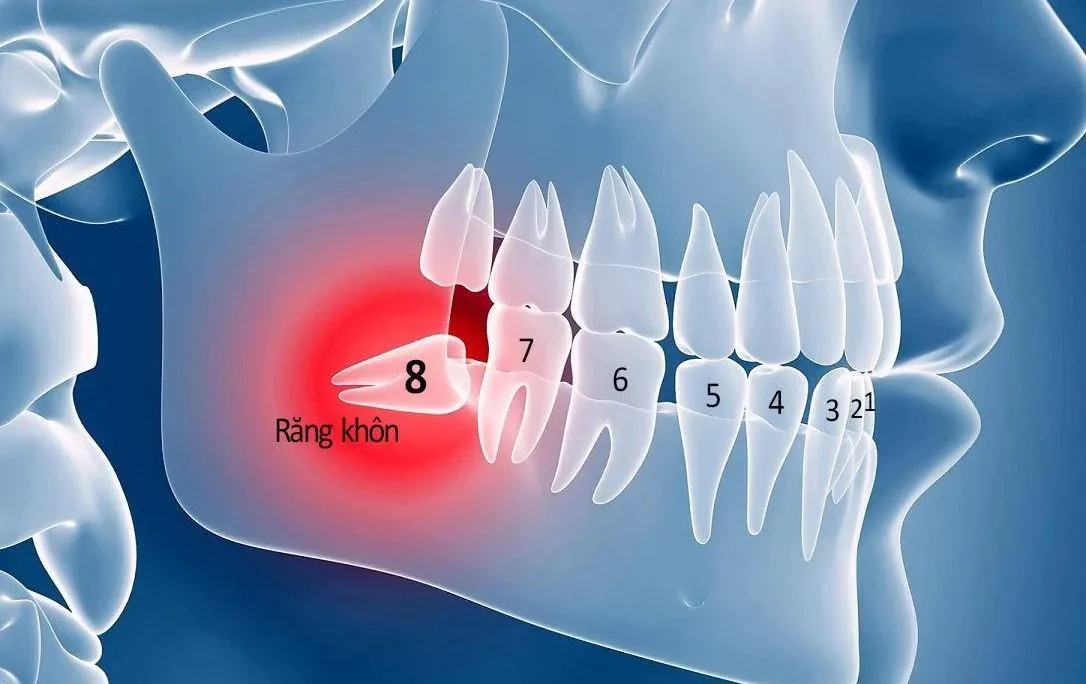

Răng bị phá vỡ khoảng sinh học

Các mô nướu xung quanh răng có tác dụng bảo vệ răng, ngăn vi khuẩn xâm nhập. Tuy nhiên, trong quá trình bọc răng sứ, nếu làm tại những đơn vị không chuyên, bác sĩ tay nghề kém sẽ mài răng và làm tổn hại sâu vào bên trong.

Điều này vô tình phá vỡ khoảng sinh học của răng và nướu, tạo điều kiện để vi khuẩn xâm nhập. Theo thời gian, bạn sẽ gặp phải tình trạng nướu sưng đỏ, viêm nướu, viêm nha chu.